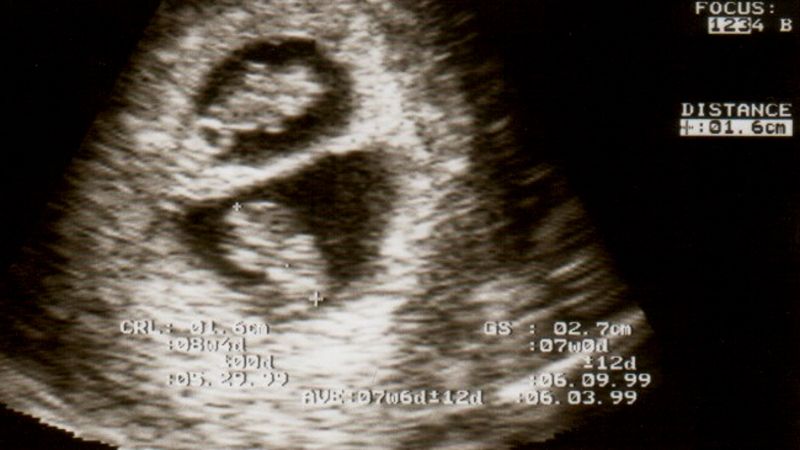

Cierpiąca na poważne zaburzenie hormonalne Australijka Kate Hill była przekonana, że nigdy nie zostanie matką. Wszystko zmieniło się jednak w wyniku bardzo rzadkiego naukowego fenomenu.

Hill i jej mężowi Peterowi urodziły się dwie córki. Charlotte i Olivia to bliźniaki jednojajowe, ale nie identyczne. W momencie narodzin różniły się wagą i grupą krwi. Inaczej przebiegał też ich rozwój płodowy.

Nie zdawaliśmy sobie sprawy co się stało, dopóki się nie urodziły. To dziwna sprawa także dlatego, że uprawialiśmy seks tylko raz. Plemniki mojego męża musiały przetrwać i potem zapłodnić drugą komórkę jajową - powiedziała szczęśliwa matka w rozmowie z "Evening Standard".

To bardzo rzadki przypadek. Natura zna jednak takie zjawiska. W tym przypadku mowa o superfetacji. Dotychczas na świecie zanotowano ok. 10 takich historii.

Przed porodem Australijka przeszła skomplikowane leczenie hormonalne. Jej niepłodność była wynikiem zespołu wielotorbielowatych jajników, bardzo częstego zaburzenia, które dotyka 10-15 procent globalnej populacji kobiet.